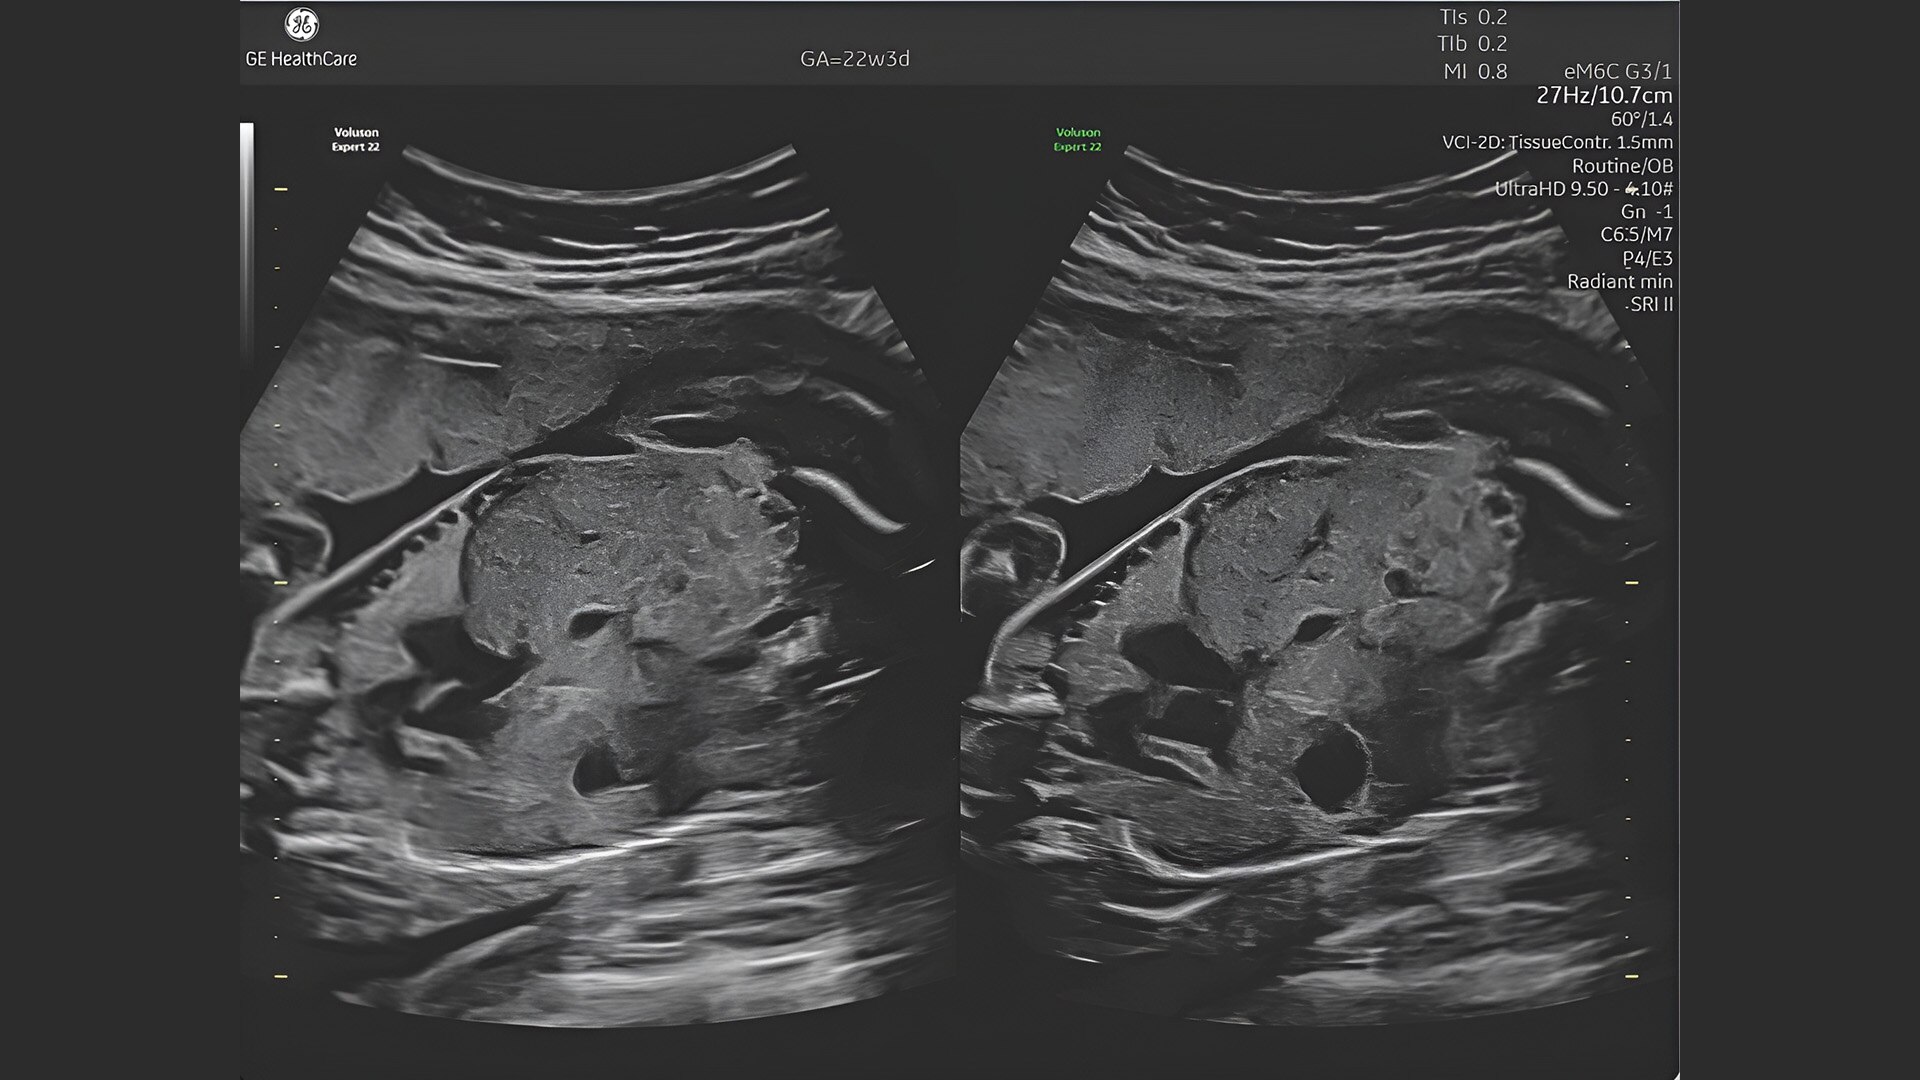

First trimester exams

Perform detailed exams with high-resolution for early insights to fetal health